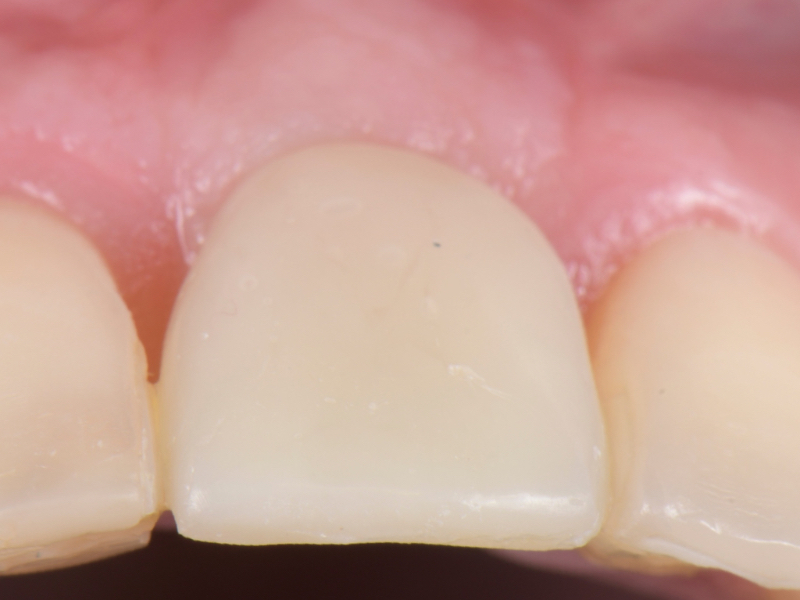

The esthetic success of an anterior implant-supported restoration mostly depends on having a soft-tissue architecture indistinguishable from the adjacent teeth. One of the most critical steps to achieve this “esthetic success” is correctly using the provisional restoration to optimize and properly contour (groom) the peri-implant tissue anatomy.

Once the optimal emergence profile has been developed, we need to communicate and transfer this information properly to the laboratory. Unfortunately, all implant companies provide stock round impression copings that do not precisely transfer the soft-tissue contours. A simple protocol to communicate this information is described here.

This visual essay walks through a step-by-step description of how to fabricate a personalized impression coping with transfer ofthe peri-implant tissue anatomy properly.